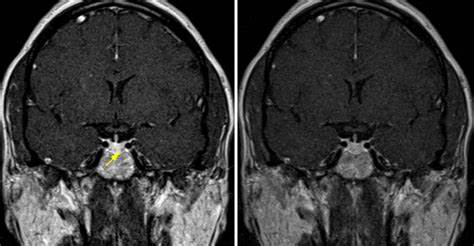

一名37岁的法国女性被发现有位于蝶鞍中央的9mm垂体瘤后,同样选择的也是神经内镜经鼻单鼻孔切除术,医生采用的是当前热门神经内镜“筷子手法”使肿瘤得以完整切除,目前正在进行相关内分泌治疗,手术后3年垂体瘤没有复发的迹象,无其他并发症。